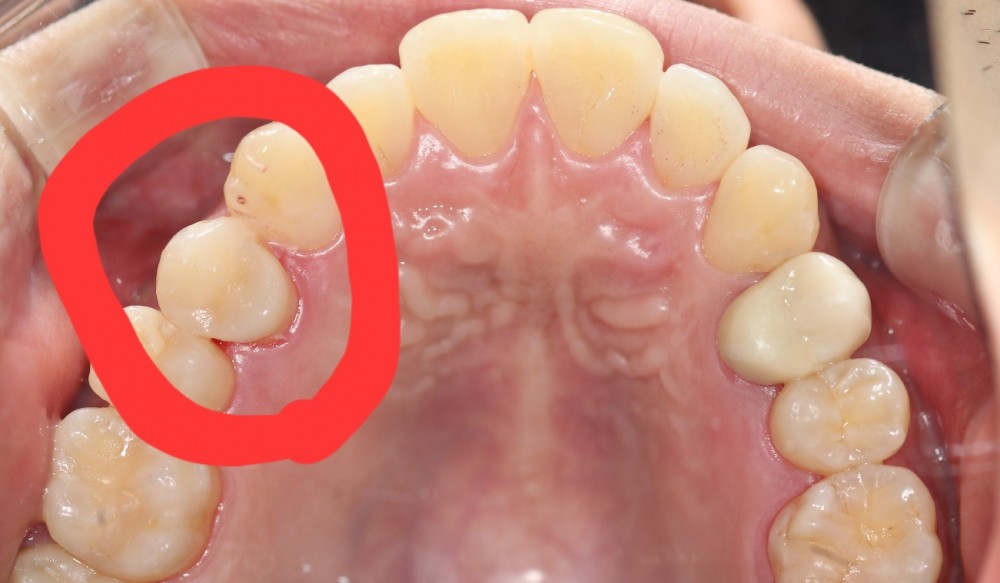

이맥스 인레이로 충치 치료하였습니다.

어느 치아가 치료한 치아일까요?

찾기 어려우시죠?

이처럼 이맥스 인레이는 아주 심미적이면서도 강도도 충분한 좋은 치료방법입니다.